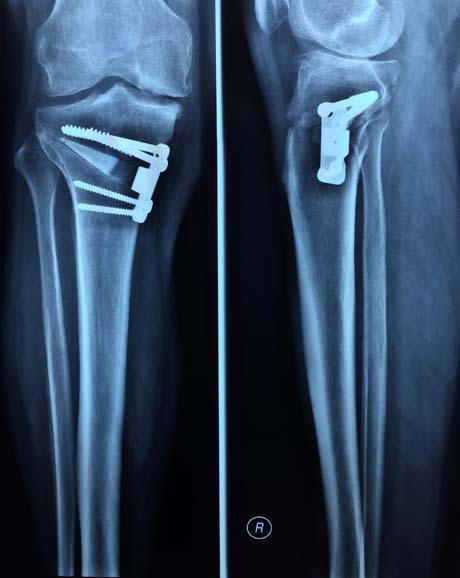

Τοποθέτηση ειδικής πλάκας οστεοτομίας (οστεοτομία βλαισότητας της κνήμης). Στο κενό του οστού εφαρμόζονται αλλομοσχεύματα και αυτομοσχεύματα

Ακτινολογικός έλεγχος αμέσως μετά το χειρουργείο

Ακτινολογικός έλεγχος δύο μήνες μετά το χειρουργείο